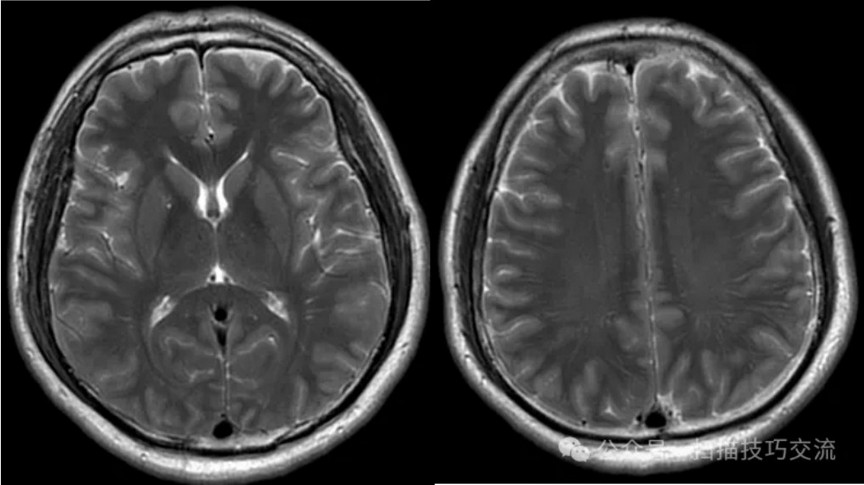

临床申请:颅脑平扫,静脉成像,磁敏感成像,颅内静脉血管黑血成像。

图像不逐一罗列,未见异常。